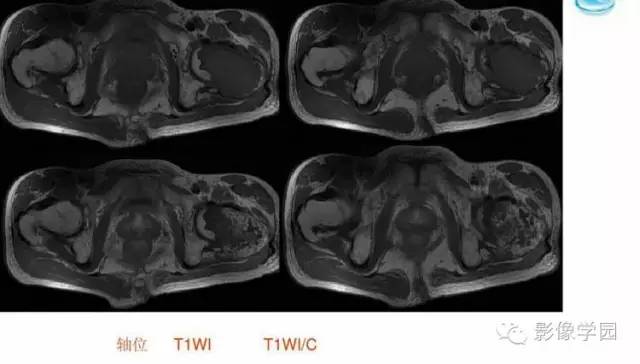

【病例】股骨软骨粘液样纤维瘤1例X线及MR影像表现